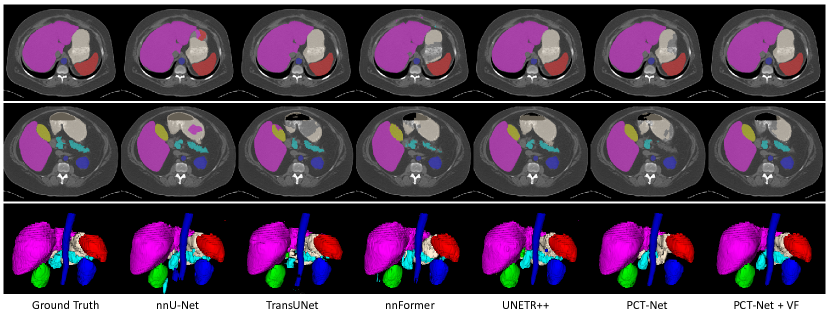

Table 5 and 6 show the quantitative evaluation of different methods on the Synapse dataset in terms of Dice and ASSD, respectively. The average Dice of nnU-Net was 87.94%, which was better than that of TransUNet (85.54%), nnFormer (86.39%) and UNETR++ (86.11%). The average Dice of PCT-Net (87.97%) was slightly higher than that of nnU-Net, and its average ASSD value (2.73 mm) was much better than that of nnU-Net (3.82 mm). When pretrained with VF, the performance of PCT-Net was further improved, with average Dice and ASSD of 89.11% and 2.04 mm, respectively. Note that nnU-Net was a strong segmentation framework. Despite that it is hard to defeat nnU-Net on all the organs, our method outperformed nnU-Net on 5 out of the 8 organs in terms of Dice, and on all the 8 organs in terms of ASSD. Fig. 8 presents a visual comparison between the segmentation results of these different methods, which shows that PCT-Net + VF achieved the best performance overall compared with the other methods.